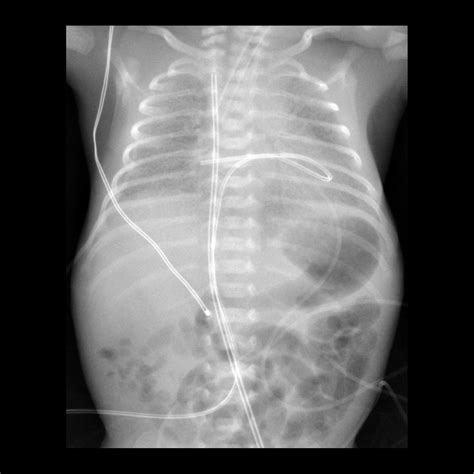

3. Insertion: The catheter is gently inserted into the umbilical vein, which is identified by its larger size and bluish color compared to the arteries. The catheter is advanced until it reaches the desired position, typically confirmed by ultrasound or X-ray.

5. Verification: The position of the catheter is verified using imaging techniques to ensure it is correctly placed in the inferior vena cava.

• Malposition: Incorrect placement of the catheter can lead to ineffective therapy or complications such as arrhythmias.

• umbilical venous catheter x ray